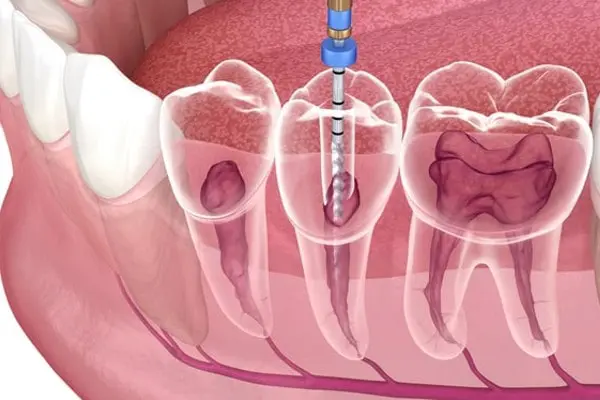

What Happens During a Second Root Canal

A second root canal procedure involves reopening the tooth, removing the previous filling material, and thoroughly cleaning the canals again. The dentist will locate any missed or infected areas, disinfect the canals, and reseal them properly.

In some cases, advanced imaging or magnification tools are used to ensure complete cleaning. After the procedure, a new crown is usually placed to protect the tooth.